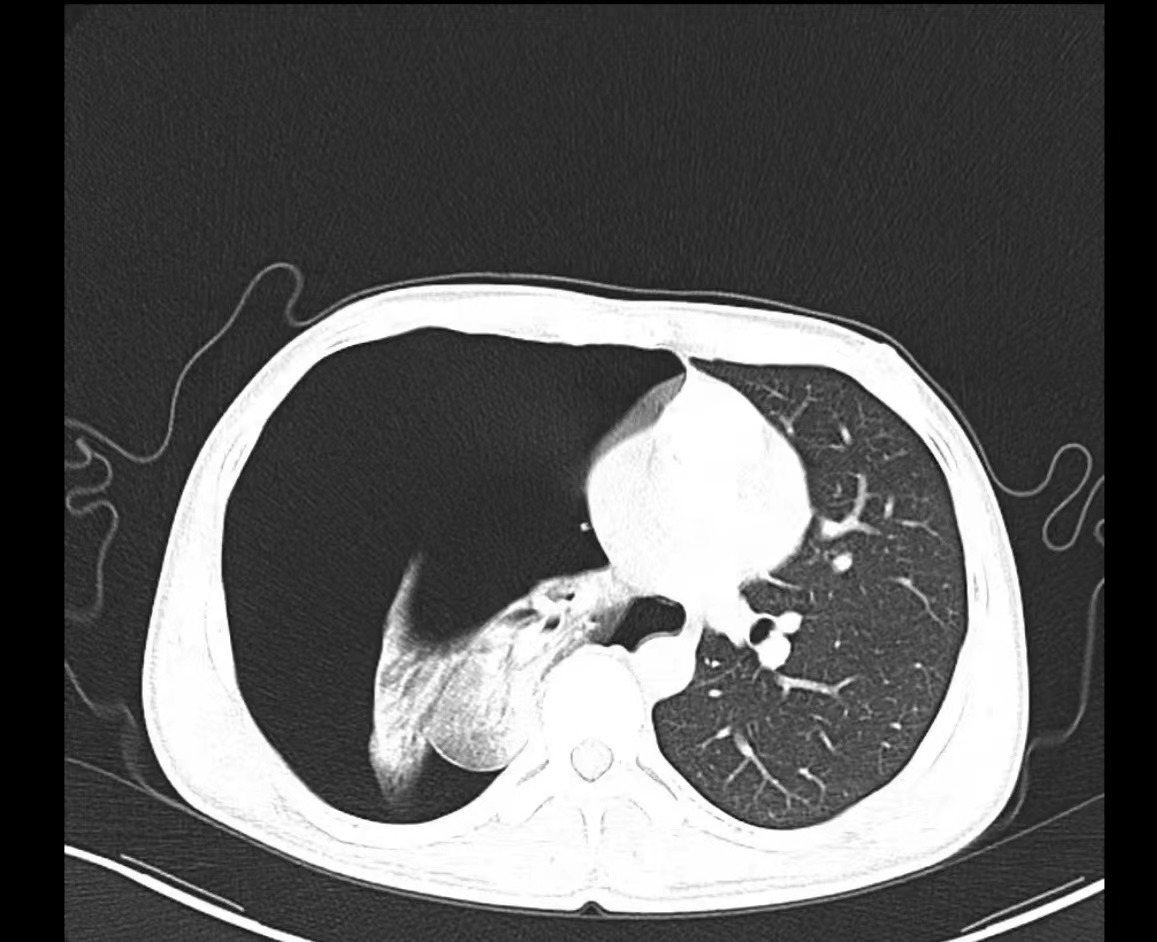

夜班急诊来了一位老大娘,捂着胸口来到CT室说:“医生,快帮我检查一下吧,看我出了什么毛病,胸口痛得厉害,出气都可疼,还闷得慌!”。于是立马登记完检查信息、赶紧给她进行CT扫描,结果一看是气胸,图像如下:

老大娘下了扫描床便说:“都怪我家那儿子,30好几了还不结婚,还没说他两句还给我顶嘴,给我气得直哆嗦,然后我就开始这样了”。看来肺还真能被“气炸”了啊!